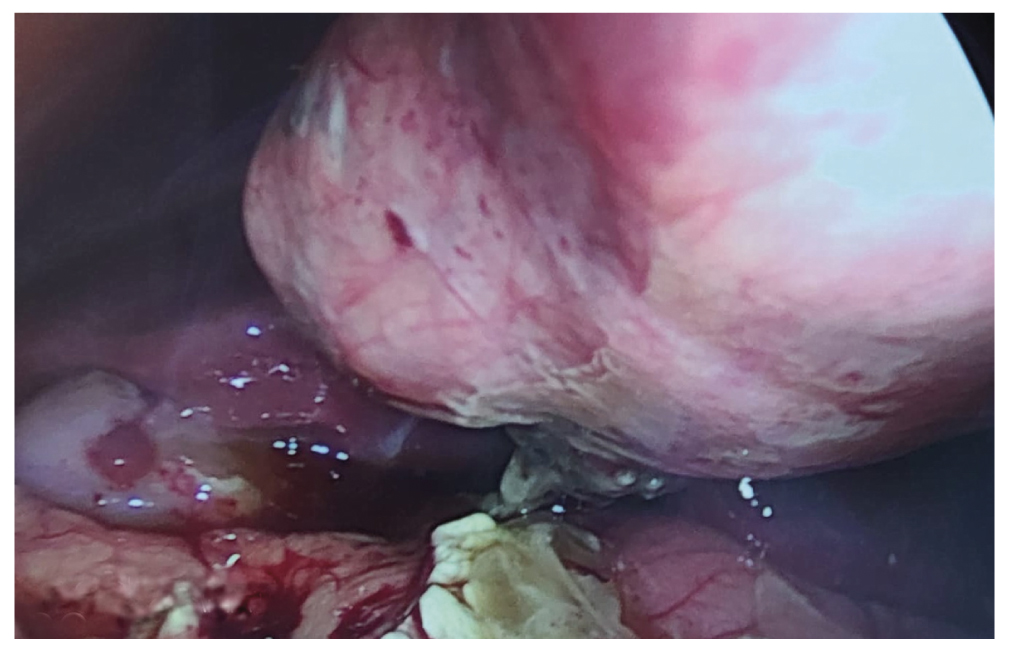

После предоперационной подготовки выполнена диагностическая лапароскопия под эндотрахеальным наркозом. В правом боковом канале и в малом тазу обнаружен выпот грязно-зелёного цвета объёмом 100 мл (рис. 1). Источник выпота не выявлен. Образец выпота взят для бактериологического посева.

Рис. 1. Выпот брюшной полости.

Fig. 1. Effusion in the abdomen.